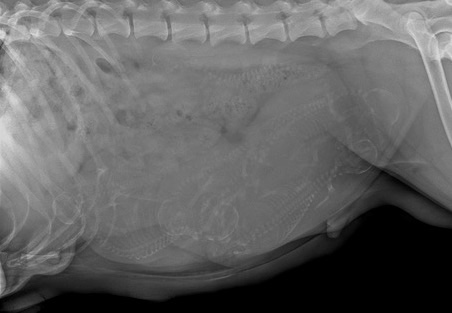

Today Tipsy went to one of our reproductive veterinarians to have an x-ray taken so that we had a general headcount of the how many puppies we should be expecting. Of course this is not 100% accurate, but it is a lot more precise than the ultrasound around 4 weeks gestation. Our lucky answer is SIX! How many do you count?